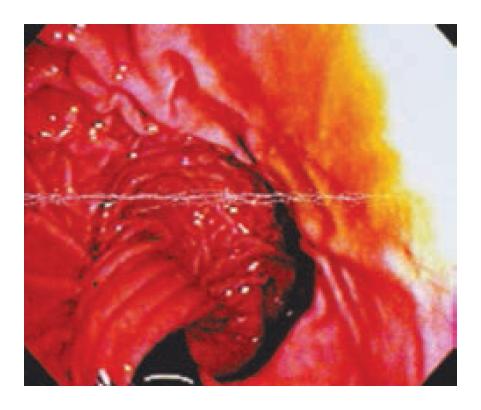

Upper gastrointestinal endoscopy is performed to assess for esophagitis, stricture, gastritis, ulceration, or tumor and to evaluate the position and integrity of the wrap. This is ideally performed before surgery. An intact fundoplication has the typical “stack of coins” appearance on a retroflexed view with the endoscope (Figure 4). Interpretation of the endoscopic findings to determine the mechanism of the failure requires experience and knowledge. For example, the presence of gastric mucosa above the wrap suggests the possibility of a slipped Nissen fundoplication. Alternatively, a widely patent gastroesophageal junction viewed on retroflexion of the endoscope positioned in the stomach suggests that the cause of recurrent symptoms may be attributed to a loose or disrupted wrap. In addition, other abnormalities such as twisted fundoplication or a two-compartment stomach may be noted (Figures 5 and 6). Identifying the squamocolumnar junction and its relation to the diaphragmatic crura can help make an assessment of esophageal length.

Figure 5

Endoscopic view of a twisted fundoplication.